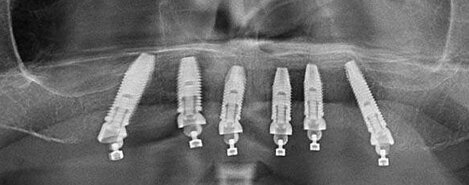

IMPLANTOLOGIA

Protesi fissa su impianti endossei

Riabilitazione orale completa con tecnica All-on-6: Inserimento di sei impianti dentali su cui viene fissata una protesi fissa, per ripristinare funzionalità ed estetica del sorriso in modo stabile e immediato.